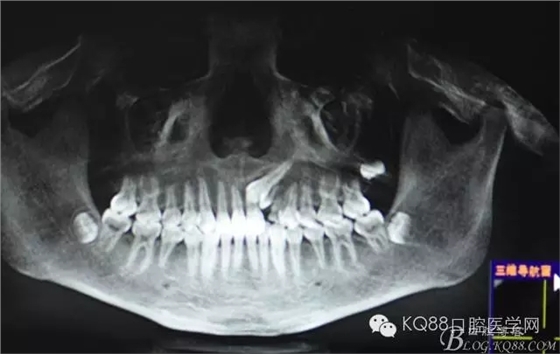

患者、王xx、男,17歲。主訴:牙齒排列不齊,要求治療。專科檢查:63乳牙滯留、22、23未萌出,cbct檢查:22牙冠畸形、過小牙,23高位埋伏阻生。正畸科治療計(jì)劃:拔除63、22,開窗正畸牽引23?;颊咄庵委煼桨福炛橥鈺?,轉(zhuǎn)診外科,拔除63、22,并行23開窗術(shù)+托槽粘接。

圖2.全景片影像檢查:23牙冠的遠(yuǎn)中還有一顆22畸形牙、及63滯留